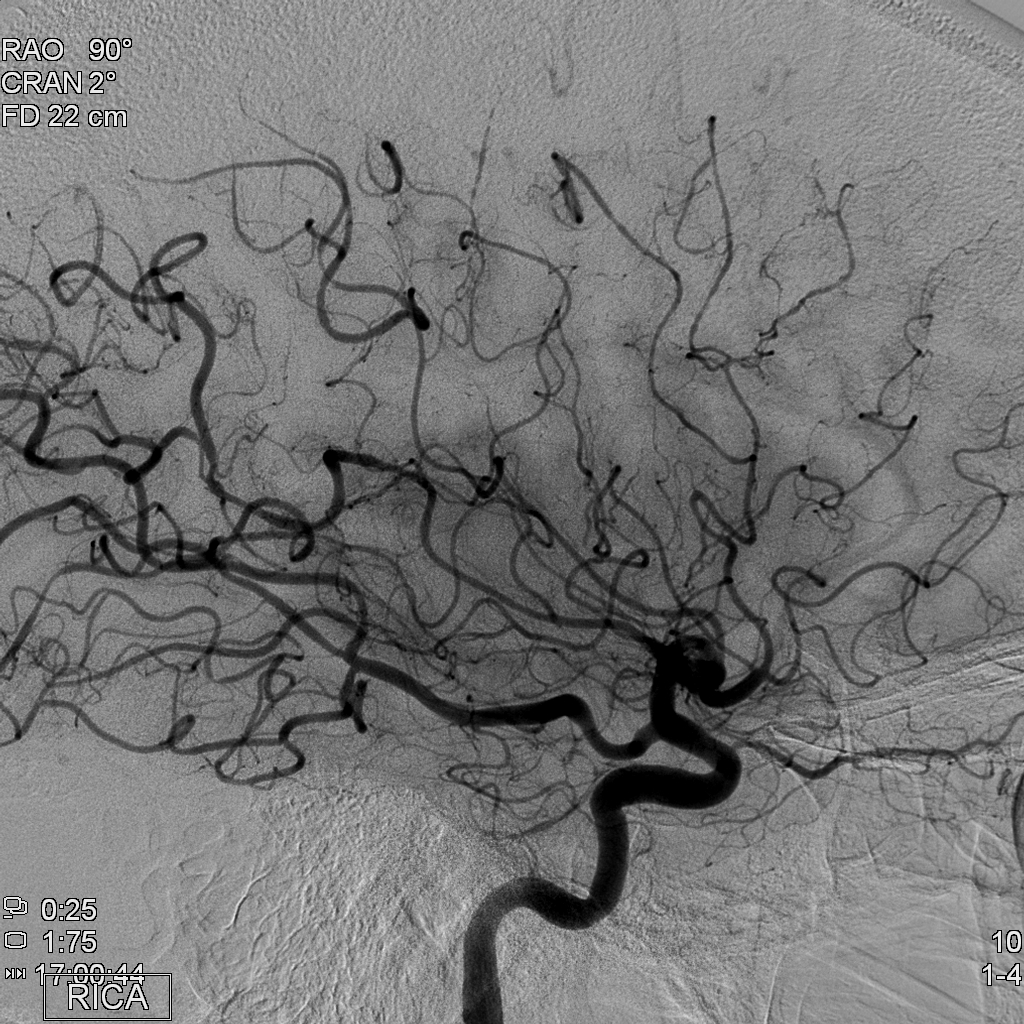

Exon-screening in Reversible Cerebral Vasoconstriction (RCVS)

Objectives: To investigate the genetic basis of RCVS using exome capture and deep sequencing.

Aim 1a: To collect DNA (from blood or saliva) from patients with RCVS using strict diagnostic criteria, and corresponding age-, ethnicity- and gender-matched controls.

Aim 1b: To collect the full set of phenotype information on RCVS.